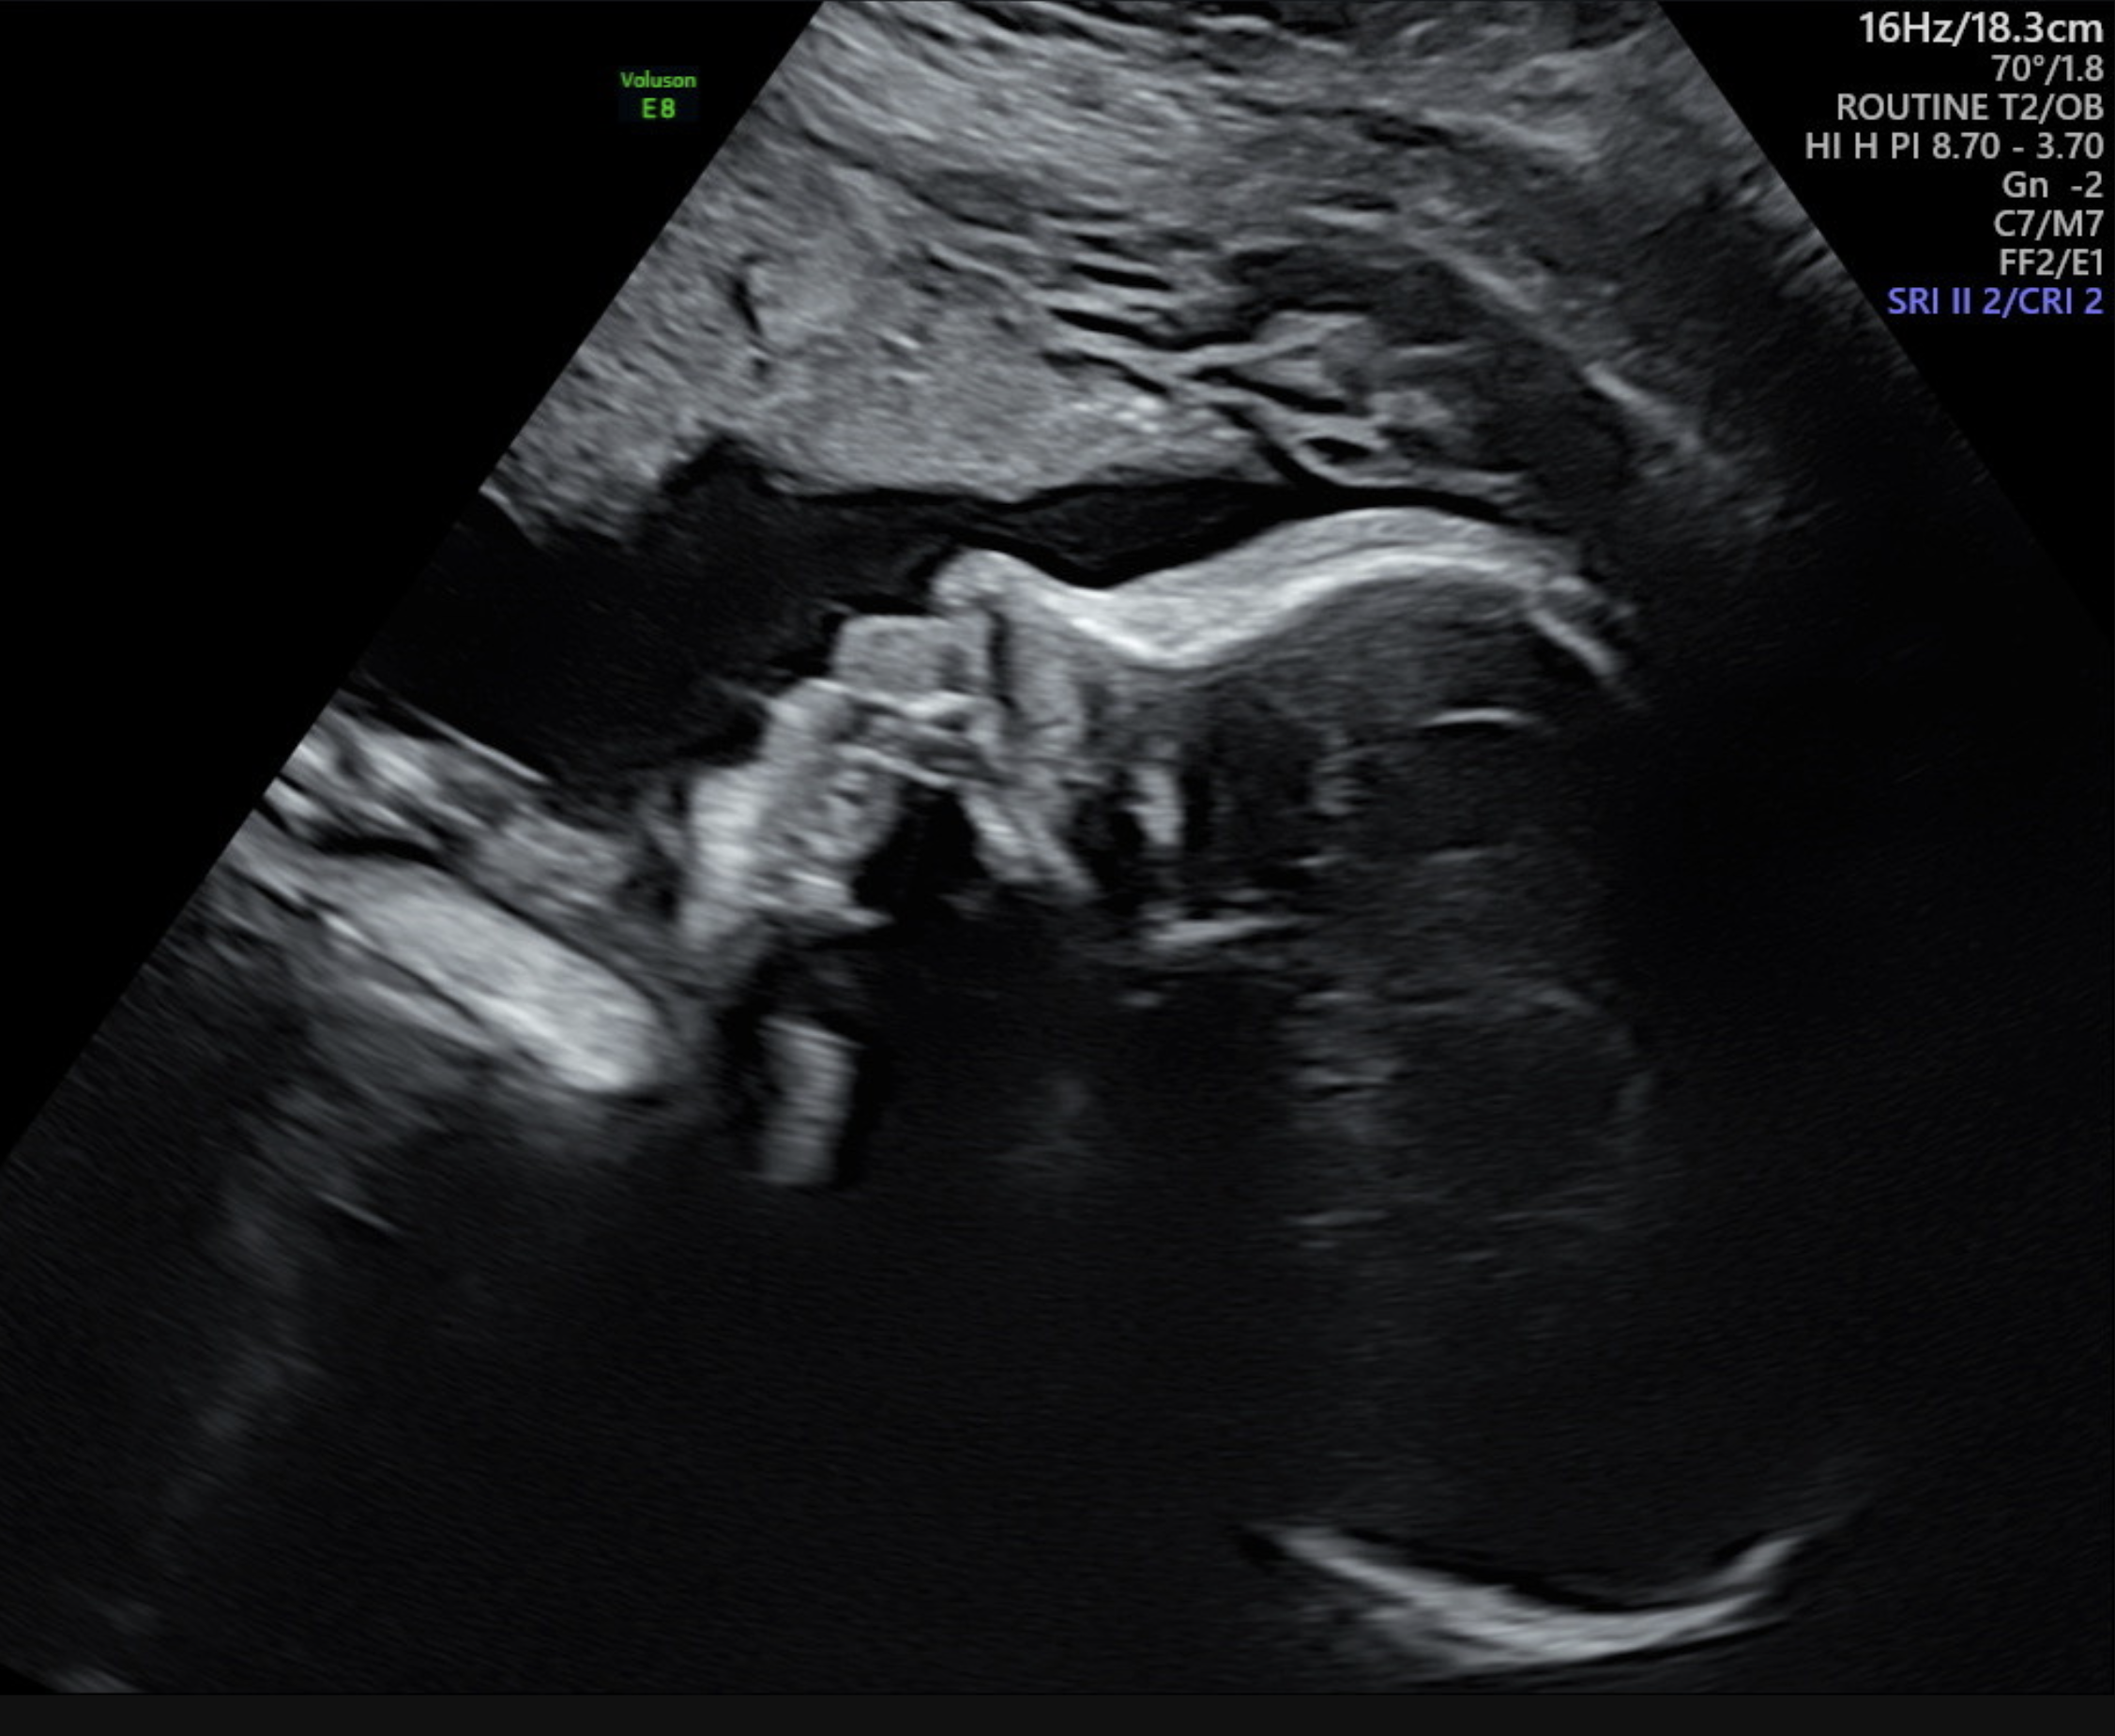

Although pregnancy is filled with happiness and joy, we understand that sometimes there are stressful moments. Our reassurance scans are here for you.

If you just want to see and bond with your baby, these scans are perfect for you. We can also provide optional individual recorded heart beat plushes of your baby’s heart rate at an additional cost.

Our reassurance scans take up to 10 minutes and include:

- Seeing and hearing baby’s heartbeat

- Seeing baby’s movement

- 2 x thermal printed hard copy images

- All pictures taken on the day straight to your mobile phone